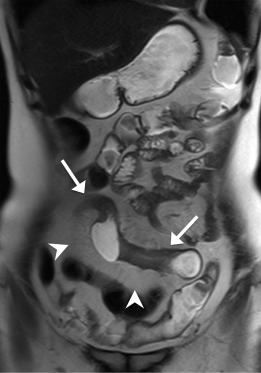

Enlarged mesenteric lymph nodes were most clearly seen on the postcontrast VIBE images, presenting as ovoid or lobulated nodular lesions between the mesenteric vessels (Figure 1 ). Engorged vasa recta were often identified adjacent to an active inflamed intestinal loop and were also best demonstrated on the postcontrast VIBE images (Figure 2 ). Fibrofatty proliferation was best seen on the coronal T2-weighted half-Fourier single-shot turbo spin-echo (T2-HASTE) images that presented as increased mesenteric fat surrounding the affected intestinal loops (Figure 3 ). Fistula tracts were often identified between an inflamed bowel and adjacent structures, showing tethering of the two structures with a contrast-enhanced fistula tract between them (Figure 4 ). Meanwhile, abscesses often manifested as fluid collections with a high signal on T2-HASTE images and well-enhanced walls on the postcontrast VIBE images (Figure 5 ).

The same patient as in Figure 1. Coronal postcontrast VIBE image shows an active ...

Figure 2.

The same patient as in Figure 1 . Coronal postcontrast VIBE image shows an active inflamed ileal segment in the right lower abdomen (arrows), with wall-thickening and increased enhancement. There are prominent engorged adjacent mesenteric vessels (arrowheads). VIBE = volumetric interpolated breath-hold examination.